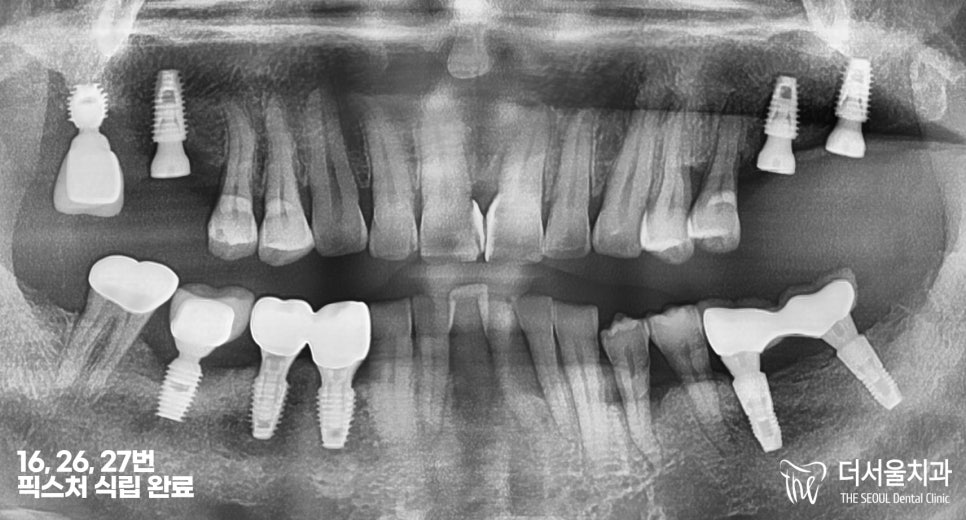

우선 16번 어금니 발치와

26, 27번 픽스처 식립은

잘 이뤄졌습니다.

픽스처 식립은 잘 마무리되었고,

뼈와 잘 결합이 이뤄지는 기간을

기다려야 되었습니다.

약 한달이라는 기간에 걸쳐

꼼꼼히 관리하고 신경쓰셔서

잘 붙은 것을 체크했습니다.

결과

깔끔하게 잘 심어졌죠?

다만 26, 27번처럼 나란히

붙어있었으면 더 좋았을 텐데,

타 원에서 심으셨던 17번은

16번과 거리가 멀어서 아쉬웠습니다.